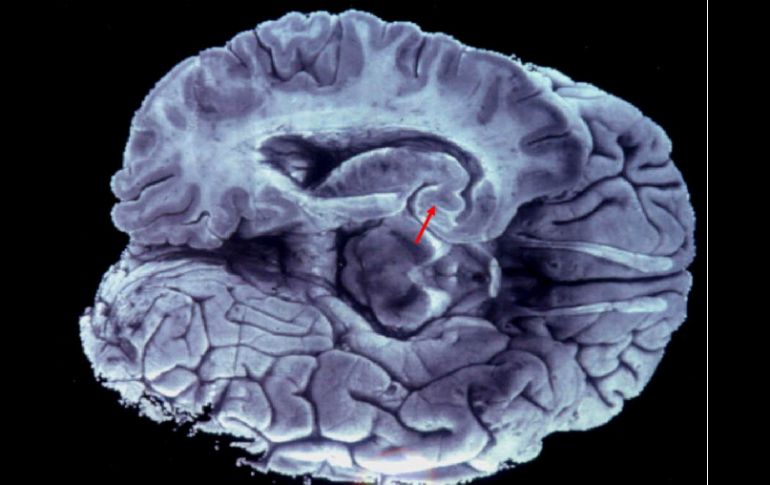

La rareza de los padecimientos ha propiciado escasa investigación sobre su origen, lo que impide la búsqueda de un tratamiento. ARCHIVO /

La rareza de los padecimientos ha propiciado escasa investigación sobre su origen, lo que impide la búsqueda de un tratamiento específico, detalló.